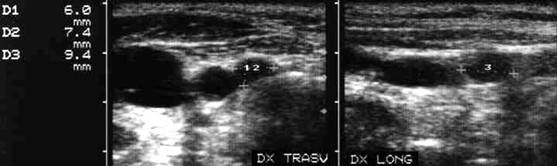

Femeie 32 ani. Nodul unic la apexul lobului drept, contur net, hipoecogen, nu influienteaza parenchimul din jur, neomogen cu arii hiperecogene si hipoecogene, de 12x17x25mm, (2,6 cc).

Citoaspiratia: leziuni foliculare.

Examen histologic postoperator: adenom microfolicular cu aspect trabecular.

ecocolordoppler si powerdoppler- acelasi nodul

Vascularizatie interna, mai evidenta in powerdoppler.